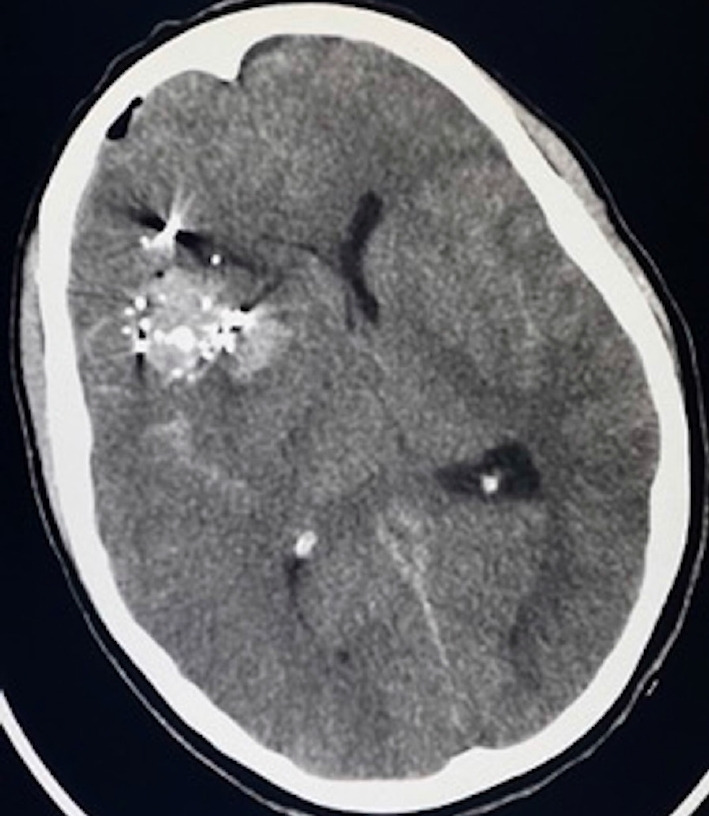

Pseudoaneurysms are rare but devastating complications of penetrating head traumas. They require rapid surgical or endovascular intervention due to their high risk of rupture; however, complex presentations may limit treatment options. Our objective is to report a case of severe vasospasm, flow diversion, and in-stent stenosis complicating the treatment of a middle cerebral artery pseudoaneurysm following a gunshot wound. A 33-year-old woman presented with multiple calvarial and bullet fragments within the right frontotemporal lobes and a large right frontotemporal intraparenchymal hemorrhage with significant cerebral edema. She underwent an emergent right hemicraniectomy for decompression, removal of bullet fragments, and evacuation of hemorrhage. Once stable enough for diagnostic cerebral angiography, she was found to have an M1 pseudoaneurysm with severe vasospasm that precluded endovascular treatment until the vasospasm resolved. The pseudoaneurysm was treated with flow diversion and in-stent stenosis was found at 4-month follow-up angiography that resolved by 8 months post-embolization. We report the successful flow diversion of an middle cerebral artery (MCA) pseudoaneurysm complicated by severe vasospasm and later in-stent stenosis. The presence of asymptomatic stenosis is believed to be reversible intimal hyperplasia and a normal aspect of endothelial healing. We suggest careful observation and dual-antiplatelet therapy as a justified approach.